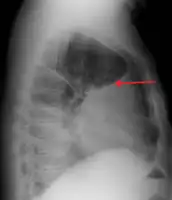

A pleural effusion appears as an area of whiteness on a standard posteroanterior chest X-ray.[9] Normally, the space between the visceral pleura and the parietal pleura cannot be seen. A pleural effusion infiltrates the space between these layers. Because the pleural effusion has a density similar to water, it can be seen on radiographs. Since the effusion has greater density than the rest of the lung, it gravitates towards the lower portions of the pleural cavity. The pleural effusion behaves according to basic fluid dynamics, conforming to the shape of pleural space, which is determined by the lung and chest wall. If the pleural space contains both air and fluid, then an air-fluid level that is horizontal will be present, instead of conforming to the lung space.[10] Chest radiographs in the lateral decubitus position (with the patient lying on the side of the pleural effusion) are more sensitive and can detect as little as 50 mL of fluid. At least 300 mL of fluid must be present before upright chest X-rays can detect a pleural effusion (e.g., blunted costophrenic angles).

A pleural effusion as seen on lateral upright chest x ray- Pleural effusion as seen behind the heart.[13]